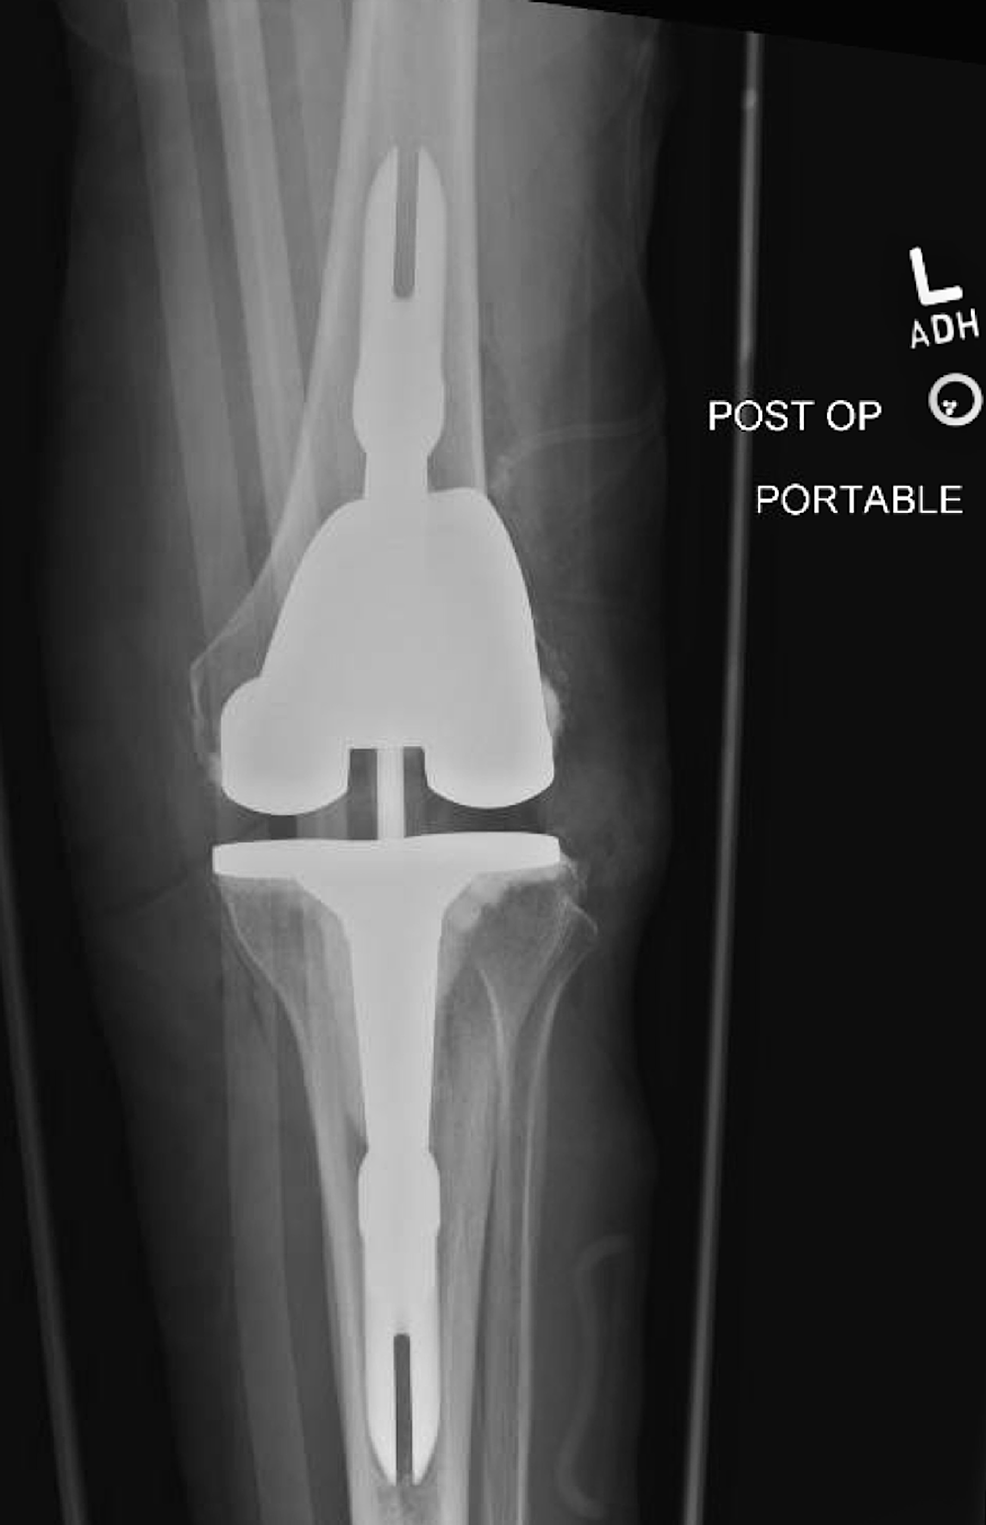

View Knee Replacement Hardware Failure PNG

View Knee Replacement Hardware Failure PNG. Diagnosis of what is causing knee pain after a knee replacement is hard to find. The first thing to look for is some type of hardware failure or pain caused by the surgery itself.